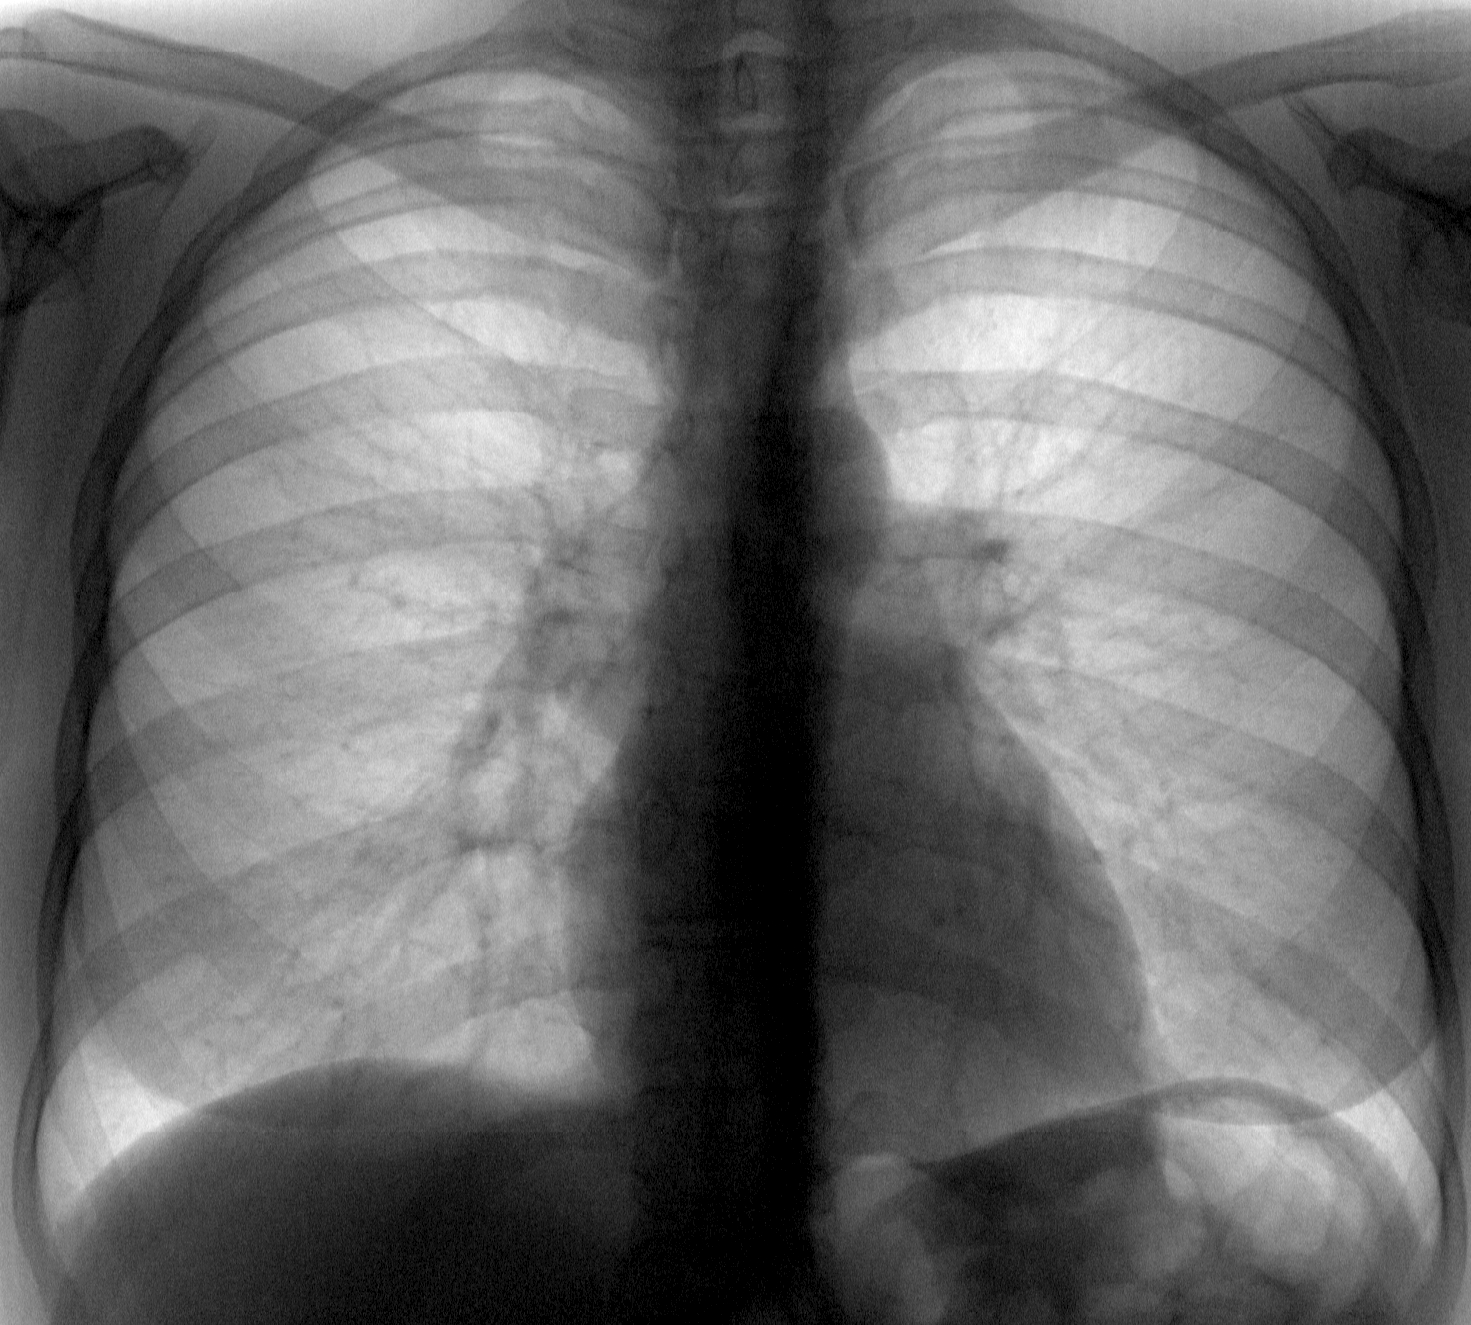

Снимок легких при туберкулезе является важным методом диагностики этого заболевания. На рентгеновских снимках можно увидеть изменения в легких, которые свойственны туберкулезу.

Рентген легких

Рентген легких

Рентген легких

Нормальная рентгенограмма ОГК

Фотографии снимков легких при туберкулезе

В данной статье представлены многочисленные фотографии снимков легких при туберкулезе, чтобы помочь вам понять, как выглядят изменения легких на рентгеновских снимках при этом заболевании.